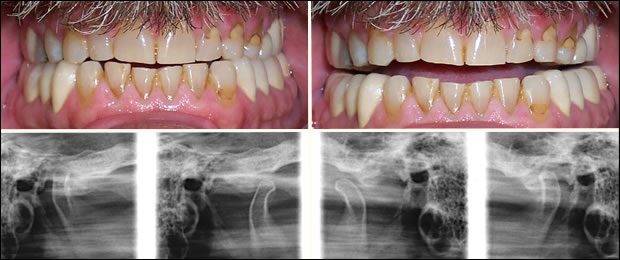

Before

Pre Op: Abraded teeth, failing restorations and collapsed vertical dimension. Pre-operative transcranial images of the temporomandibular joints, closed and open, right and left respectively.